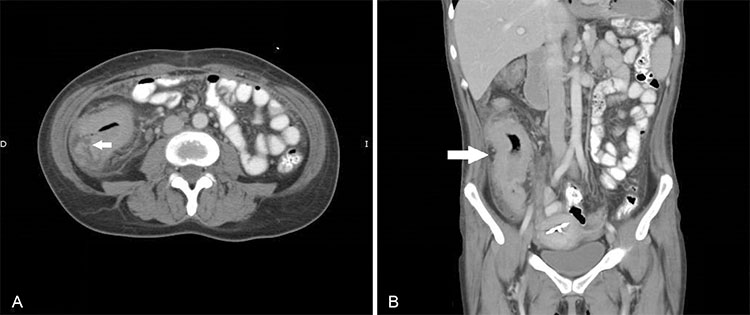

En los pacientes con TBC abdominal, el compromiso a nivel ileocecal se presenta en un 80% a 90% de los pacientes.13 En TC, la mitad de los pacientes con tuberculosis gastrointestinal muestran engrosamiento circunferencial del ciego e íleon terminal, ampliación de la válvula ileocecal, y linfoadenopatías mesentéricas (Fig. 7).8 Hallazgos como la asimetría de la válvula ileocecal, engrosamiento de la pared medial del ciego, la extensión exofítica e inmersión del íleon terminal, asociado a múltiples adenopatías son más sugestivos de tuberculosis.6,13,14

Mujer de 40 años hospitalizada por sospecha de TBC intestinal, se solicita TC que destacó: (a) severo engrosamiento parietal difuso y concéntrico del íleon distal, que no estenosa significativamente el lumen y compromete la válvula ileocecal (flecha). Existe aumento de densidad de la grasa mesentérica y pericecal adyacente con pequeñas adenopatías de baja densidad de la cadena ileocólica que miden hasta 8 mm de diámetro. (b) La pared intestinal alcanza un espesor de 13 mm y realza en forma homogénea por contraste.